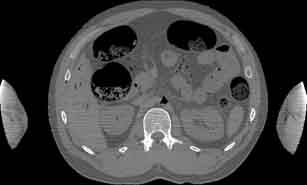

Visible Human male: Sectio transversalis 1594

CT

NMR

Pd                          / T2 \                         T1